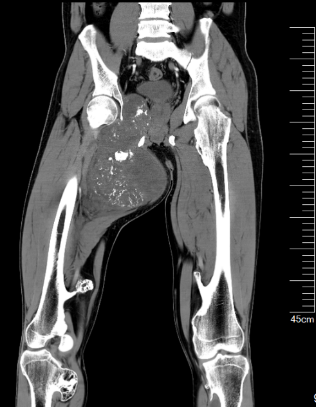

通过3D建模的精准评估,小王右耻骨软骨肉瘤体积达到了1600立方厘米(1600623.71立方毫米),肿瘤下极自右大腿中段向上,内侧贴大腿皮肤,外侧推压内收肌群及股动静脉,穿过骨盆右闭孔,紧贴右髋臼内侧壁生长,骨盆内占位部分推压膀胱。

患者的肿瘤累及右侧耻骨上下支(Enneking Ⅲ区),预计截骨范围为耻骨联合到耻骨上支、耻骨下支到坐骨体内侧。由于肿物体积巨大,无论采用髂股入路还是髂腹股沟入路,单纯前路手术很难暴露坐骨及髋臼后柱结构,而在前路强行提拉推压肿物则会增加肿瘤破裂的风险。通过延伸Gibson入路,可以清晰的显露坐骨支,完整地显露截骨边界,降低肿瘤破裂及血管损伤的风险。由于该部分区域为非负重区,因此,无需进行骨盆环重建,但需要注意盆壁的修补,预防盆腔器官受重力作用下垂相关并发症。

通过MDT诊疗模式,我院骨科团队联合麻醉科、重症医学科、肿瘤内科、放射科等科室共同制定了完善的治疗方案。手术采用髂腹股沟入路联合Gibson入路,在前路游离保护股动静脉及股神经,离断耻骨联合,并向远端剥离出肿瘤下界、外侧边界及内侧边界;改左侧卧位后,经Gibson入路首先游离保护坐骨神经,截断坐骨结节使肿物松动后再次转回仰卧位继续分离至肿瘤上边界,完整切除整块肿物,送病理检查,继续重建坐骨结节处股二头肌长头起点,修复盆底结构,至此,手术顺利完成。